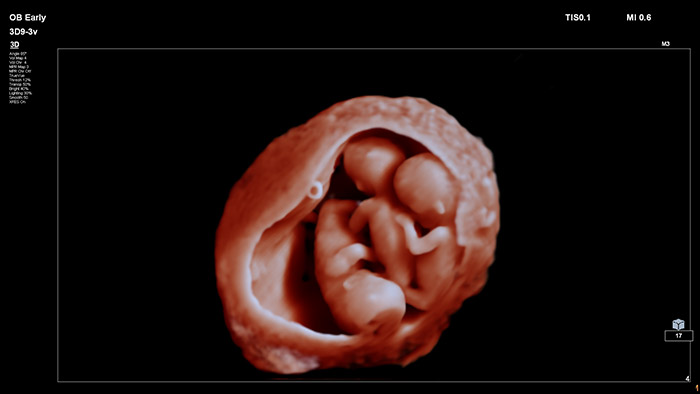

In this video Dr. Michael Ruma of Perinatal Associates New Mexico, explores the use of Philips TrueVue Pro, TouchVue, MPR Touch, Touch Sculpt, Touch Erase, Touch Zoom and aReveal for OB/GYN exams.

In this video Dr. Michael Ruma presents FlexVue and RexVue Volume, Philips advanced 3D evaluation tools. FlexVue and Flexvue Volume allows for easy visualization of technically difficult anatomical views from 3D volumes that are essential for diagnosis of OB/GYN pathology

In this video Dr. Michael Ruma presents FlexVue and Orthogonal View, Philips advanced 3D evaluation tools on clinical cases for OB and GYN.

Pairing the new V9-2 transducer with the EPIQ Elite premium ultrasound system offers next-level Ob/Gyn imaging:

Advanced obstetric visualization tools for photorealistic fetal rendering.